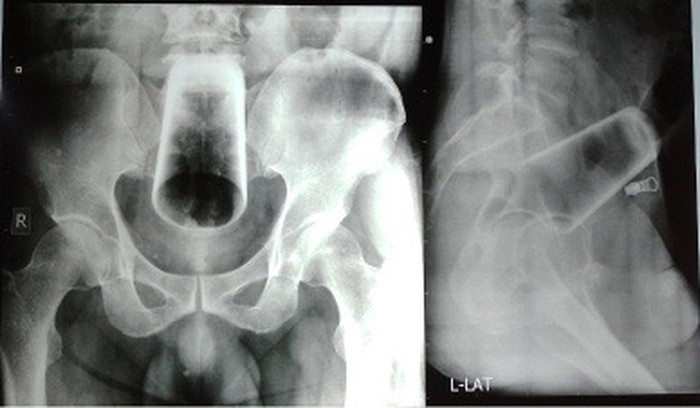

Demi kepuasan seksual, seorang remaja berusia 12 tahun di China nekat masturbasi menggunakan termometer. Akibatnya, termometer tersebut tersangkut dalam kandung kemih.

Dokter akhirnya berhasil mengangkat termometer tersebut dari tubuhnya melalui operasi. Terlepas dari itu, tidak ada kabar mengenai apakah remaja tersebut mengalami komplikasi imbas dari eksperimennya. (Foto: Asian Journal of Surgery)